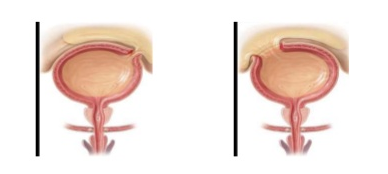

Tępy uraz pęcherza moczowego, przepełnionego - najczestsza lokalizacja w pęcherzu i powikłanie

Szczyt pęcherza, skutkuje wylaniem moczu do jamy otrzewnowej ( w tym miejscu pęcherz jest pokryty otrzewną)

Urazy miednicze - jaka częśćpęcherza uszkodzona i jakie powikłanie?

Dolna, pozaotrzewnowa część pęcherza.

Powikłanie : zaciek moczowy, krwiak, deformacja i przesunięcie pęcherza

Wewnątrzotrzewnowe uszkodzenie pęcherza - objawy

Objawy typowe dla zapalenia otrzewnej - obrona mięśniowa, objaw Blumberga, porażenie perystaltyki jelit

Zewnątrzotrzewnowe uszkodzenie pęcherza - objawy

Brak objawów otrzewnowych, zaciek moczowy, bolesność uciskowa nad spojeniem łonowym, póżniej - ropowica krocza, moszny, pachwin